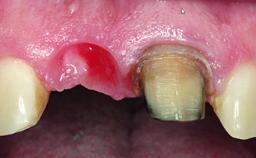

Replacement of an Upper Right Central Incisor with Root Resorption: Ridge Preservation, Early Placement of an RC Bone Level Implant

A 49-year-old female patient was referred for implant therapy to replace the upper right central incisor (tooth 11). The tooth had been assessed by an endodontist who diagnosed a vertical fracture of the root. The tooth had a hopeless prognosis and needed to be extracted. The patient was healthy and was not taking any medications. She was allergic to penicillin. The patient had high esthetic demands but her expectations were realistic. The extraoral examination revealed no facial asymmetries. The right temporomandibular joint demonstrated an opening click but was otherwise asymptomatic. The lip line was high with a significant gingival display.

Bone Augmentation Simultaneous|Vertical

Augmentation Materials Autogenous chips|Xenogenous|Membrane